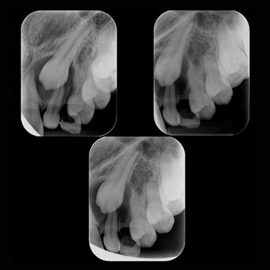

Radiografia Periapical

Indicada para estudos individuais ou de grupos de dentes, proporcionando uma visão da anatomia dentária (coroa e raiz) e estruturas que circundam o dente (espaço articular, osso alveolar e demais estruturas anatômicas), com excelente resolução.

técnica-de-localização

Técnica de Localização Radiográfica

Técnica que através de incidências radiográficas em angulações diferentes, permite dissociar imagens de estruturas sobrepostas como dentes inclusos, corpos estranhos e dentes multiradiculares, indicando sua localização e avaliação do acesso cirúrgico.